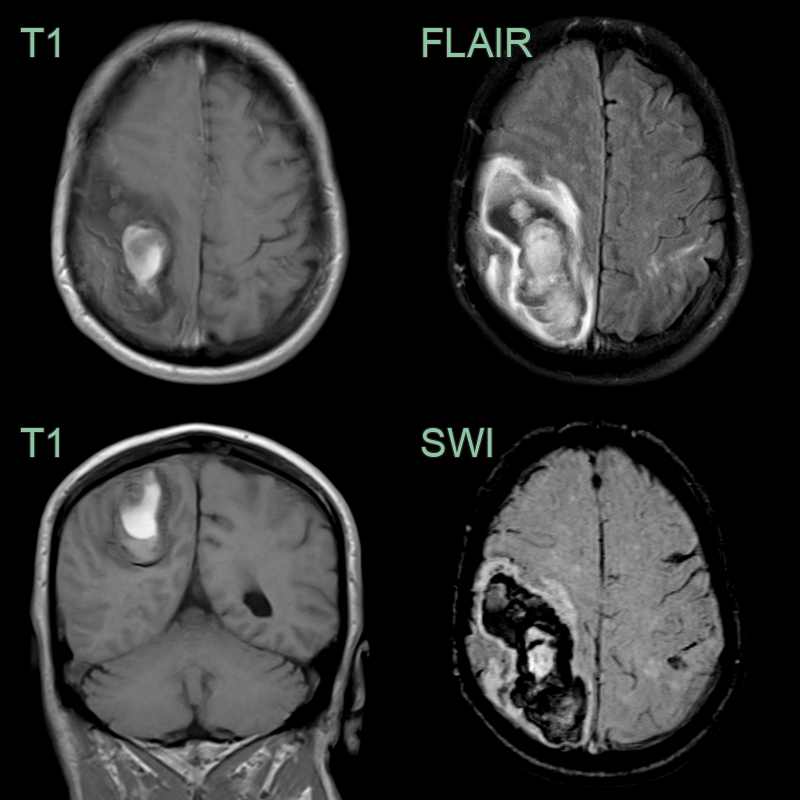

• A 65-year-old patient presented with headache and left sided weakness.

• MRI showed a large lobar hematoma in the right parietal lobe.

• There was a trace of acute blood in the left post-central gyrus (based on FLAIR hyperintensity).

• While there were no white matter features of CAA, the combination of the superficial siderosis over the left frontal lobe and the lobar hematoma were sufficent to meet criteria for probable CAA.